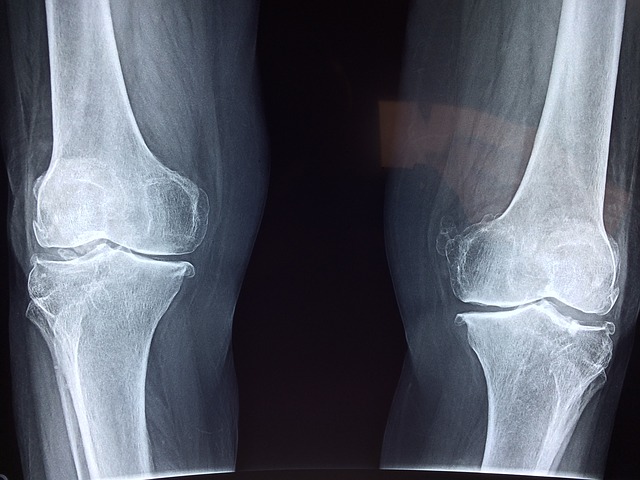

לאחר שתלכו אל האורטופד ותפרטו בפניו את הבעיה הוא יבצע שלל בדיקות אשר יאפשרו לו לאתר את הבעיה. רק לאחר איתור הבעיה ואבחונה יוכל האורטופד להמליץ לכם על הטיפול הטוב ביותר בשבילכם. האורטופד יוכל להמליץ על טיפול תרופתי, על טיפולי פיזיותרפיה ובמקרים מסוימים אף על החלפת מפרק הברך או ניתוח מסוג אחר וזאת בכדי לטפל בבעיית הברכיים. באמצעות פניה אל האורטופד תבטיחו כי הטיפול בכם יהיה אפקטיבי ויעיל ותבטיחו כי תוכל לחזור לשגרה בסוף הטיפול.